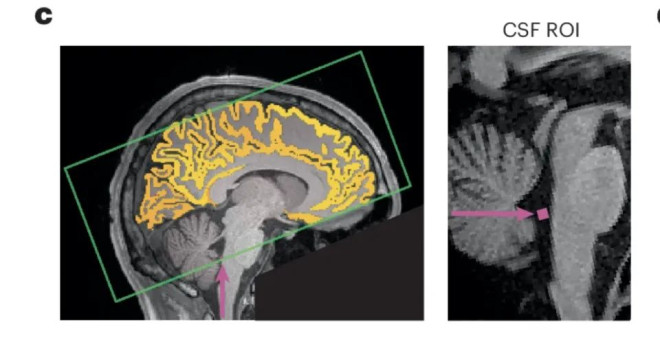

2025 年 10 月发表在《自然神经科学》杂志上的一篇研究指出,熬夜后的注意力不集中,可能是因为你的大脑正在给自己“洗澡”。

脑科学界这几年有个新理论:大脑会在白天产生代谢废物,在睡眠时通过脑脊液不断冲刷、清除掉,从而让大脑再次恢复清洁。

比如大名鼎鼎的大脑代谢废物——阿尔茨海默症的罪魁祸首——淀粉样蛋白,就是在这个过程中被清除干净的。

正常情况下,脑子会在深度睡眠时清除掉代谢废物,但熬夜没睡够,大脑又不能放着不洗,那就只能“白天上班时偷偷洗澡”了。

研究人员找来了 26 位成年人,让他们在一次实验中睡得很好,另一次则整晚不睡。不出意外,熬夜的那次,简单的注意力测试表现很差。

有趣的是,通过脑部 MRI 扫描发现:

每次注意力“断片”的前 2 秒,脑脊液会被冲出脑底;而注意力恢复后的 1 秒,又会被重新吸回大脑。

也就是说,你在发呆、走神的时候,大脑正在进行“紧急冲洗”。

研究者形容:“这就像洗衣机——先加水,再搅动、再排水。注意力走神时,大脑正好在‘搅’。

研究人员也说了:睡觉时清理才是最优方案,强行白天补洗,不仅效率低,还直接影响认知表现。